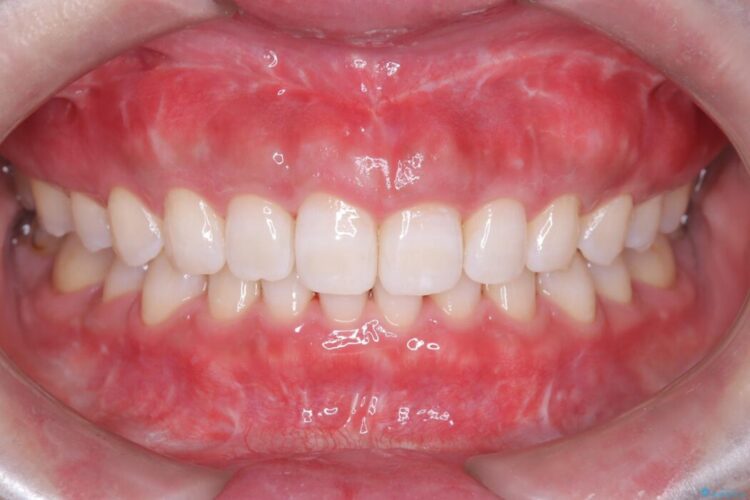

長期的な安定性を重視したセラミック治療

歯と歯の間に虫歯があった患者様です。

治療期間(治療回数):1ヶ月(2~5回) | 概算治療費:13.2万円(税込)(仮歯:10,000円+オールセラミッククラウン 3年保証110,000円)